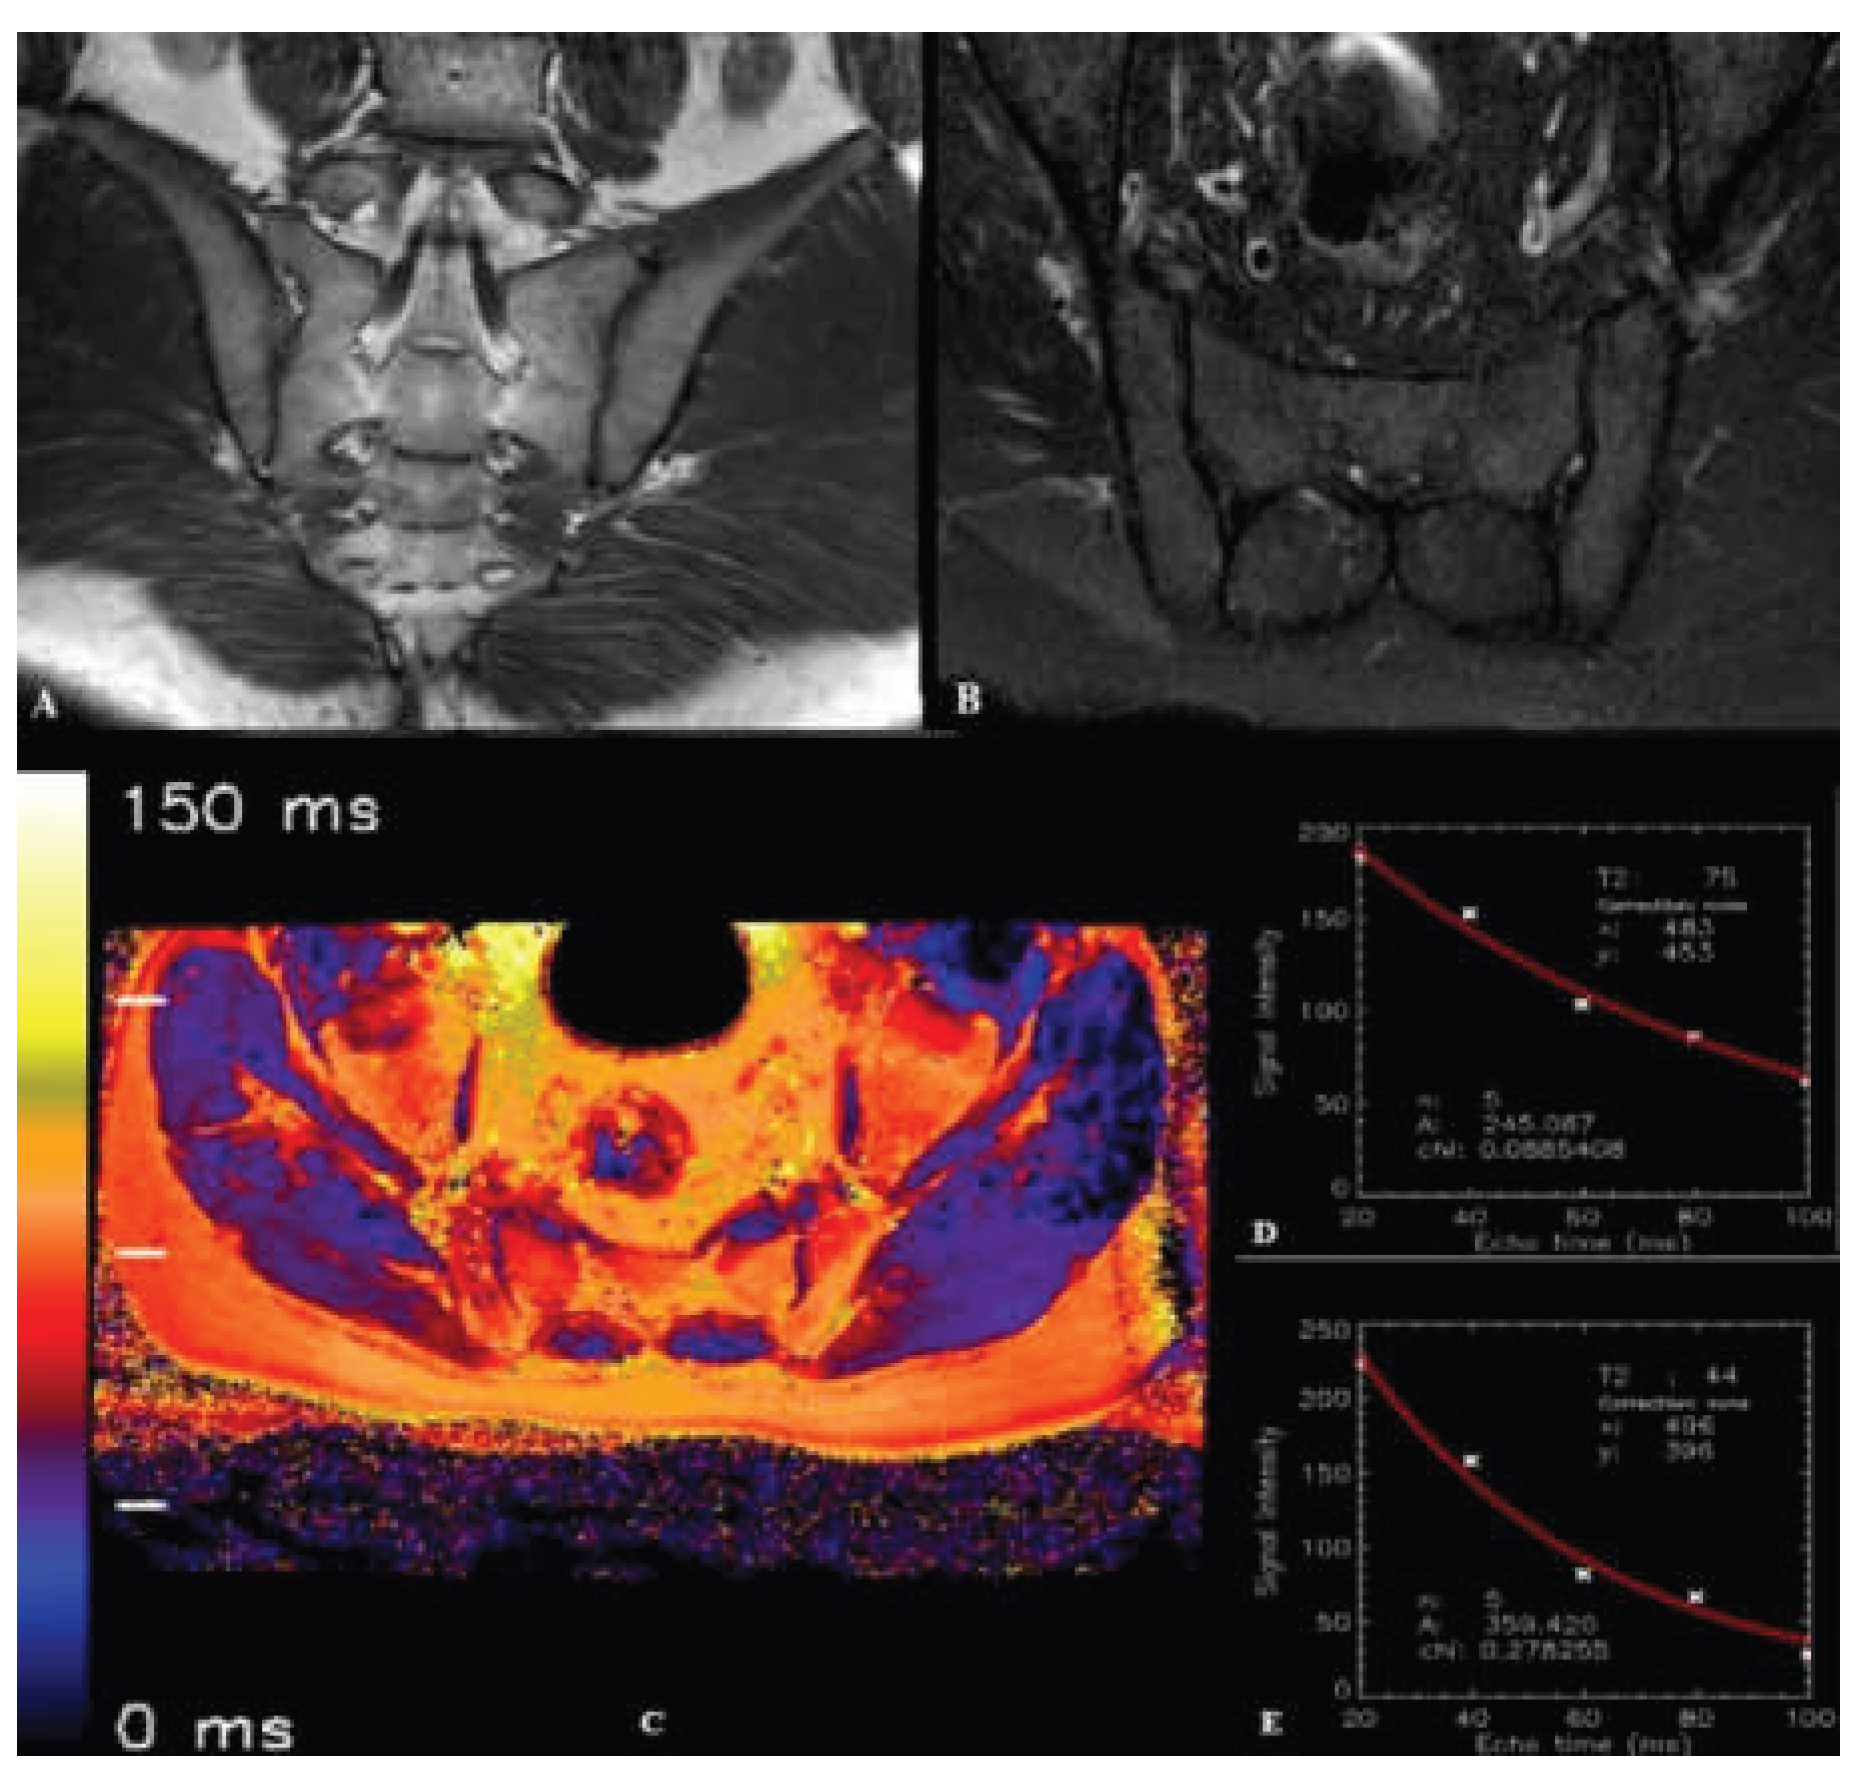

- Wang, D.; Yin, H.; Liu, W.; Li, Z.; Ren, J.; Wang, K.; Han, D. Comparative analysis of the diagnostic values of T2 mapping and diffusion-weighted imaging for sacroiliitis in ankylosing spondylitis. Skeletal Radiol 2020, 49, 1597–1606. [Google Scholar] [CrossRef] [PubMed]

- Messroghli, D.R.; Rudolph, A.; Abdel-Aty, H.; Wassmuth, R.; Kuhne, T.; Dietz, R.; Schulz-Menger, J. An open-source software tool for the generation of relaxation time maps in magnetic resonance imaging. BMC Med Imaging 2010, 10, 16. [Google Scholar] [CrossRef] [PubMed]

- SourceForge. MRmap v1.4. Available online: https://sourceforge.net/p/mrmap/mailman/message/30100362/ (accessed on January, 2021).

- Albano, D.; Bignone, R.; Chianca, V.; Cuocolo, R.; Messina, C.; Sconfienza, L.M.; Ciccia, F.; Brunetti, A.; Midiri, M.; Galia, M. T2 mapping of the sacroiliac joints in patients with axial spondyloarthritis. Eur J Radiol 2020, 131, 109246. [Google Scholar] [CrossRef]